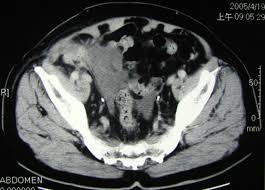

Can Colon Cancer Be Mistaken For Hernia : Female Hernias Can Be Misdiagnosed Or Overlooked Prime Surgicare : I was diagnosed in april2019, and had my first surgery on 5/6 (opensurgery), with a second one 10 days later due to an anastomotic leak.. Some of the other medical conditions that can be confused with appendicitis include: A hernia happens anytime a body part pushes into a place where it doesn't belong. It should not be mistaken for a pericolic abscess and, where there is the slightest doubt, percutaneous drainage should be contraindicated. Due to the widely misunderstood nature of cancer, cancer misdiagnosis is among the most common type of medical misdiagnosis. We therefore conclude that the association between colon cancer and inguinal hernia is mainly coincidental, and the cancer must be suspected on a clinical basis.

Pdf An Unusual Case Of A Strangulated Right Inguinal Hernia Containing The Sigmoid Colon from i1.rgstatic.net Shelby is very active on our site always there to help others along their way, offering support and answering questions that those who are just starting. It may lead to immediate death, so you have to know symptoms and early warning signs of colon cancer to protect yourself against this disaster. An inguinal hernia containing colorectal cancer is rare but serious and can often present with complications such as perforation. In this condition, pain is caused on the left side of the abdomen but it can also be at the right side, which is quite close to the location of the appendix. Because hernias are more common in men than in women, they can sometimes be an overlooked source of pain for women, according to the society of laparoendoscopic surgeons (sls). A hernia happens anytime a body part pushes into a place where it doesn't belong. A tumor is a solid or cystic mass. The use of synthetic mesh in association with colonic resection did not lead to post operative infection, allowing concomitant treatment of both diseases in elderly, high risk patients.

We therefore conclude that the association between colon cancer and inguinal hernia is mainly coincidental, and the cancer must be suspected on a clinical basis. Less than 1 out of 200 cases of crc is localized within an inguinal hernia 6 . It may lead to immediate death, so you have to know symptoms and early warning signs of colon cancer to protect yourself against this disaster. Colon cancer is a very critical issue and maybe one of the causes of sudden death in young men, women and elderly. I performed an scope examination of her esophagus and confronted a huge cancer occupying the lower portion of her esophagus. The use of synthetic mesh in association with colonic resection did not lead to post operative infection, allowing concomitant treatment of both diseases in elderly, high risk patients. In the region of the inguinal canal, where most hernias occur, there are lymph nodes that can enlarge from infectious or malignancies, and can be mistaken for a hernia. When a hernia meets cancer. A tumor is a solid or cystic mass. A female patient came to see me with some difficulty swallowing, a very routine issue for a gastroenterologist. When colon cancer is detected in its early stages, there may be no symptoms present at all. Typically, patients with ventral hernias describe mild pain, aching or a pressure sensation at the site of the hernia. As detailed in the risk factors, acid reflux caused by hiatal hernia is one of the main cause of esophageal cancer.

Although still considered rare, adenocarcinoma of the esophagus, the most common form of esophageal cancer, is one of the. Since a hiatal hernia often exhibits the same symptoms as other conditions, it can be easily mistaken for something else entirely. De caestecker discusses hernia symptoms and what they might be mistaken for. Initial common symptoms in patients presenting with colon cancer are abdominal pain, change in bowel habits, melaena, and general weakness 5 . Colonoscopy, a procedure which involves a flexible tube with an attached video camera. Some of the other medical conditions that can be confused with appendicitis include: In cases where cancer is not identified or mistaken for another disease, patients may miss a critical window for treatment. As detailed in the risk factors, acid reflux caused by hiatal hernia is one of the main cause of esophageal cancer. Many conditions can cause hip pain, and cancer is one of them. An inguinal hernia containing colorectal cancer is rare but serious and can often present with complications such as perforation. Less than 1 out of 200 cases of crc is localized within an inguinal hernia 6 . Do not hesitate to consult your cancer doctor immediately and visit a colon cancer center if you suffer from any of these warning signs. She is an endometrial cancer survivor and is starting to get compfortable with the idea of being a survivor.